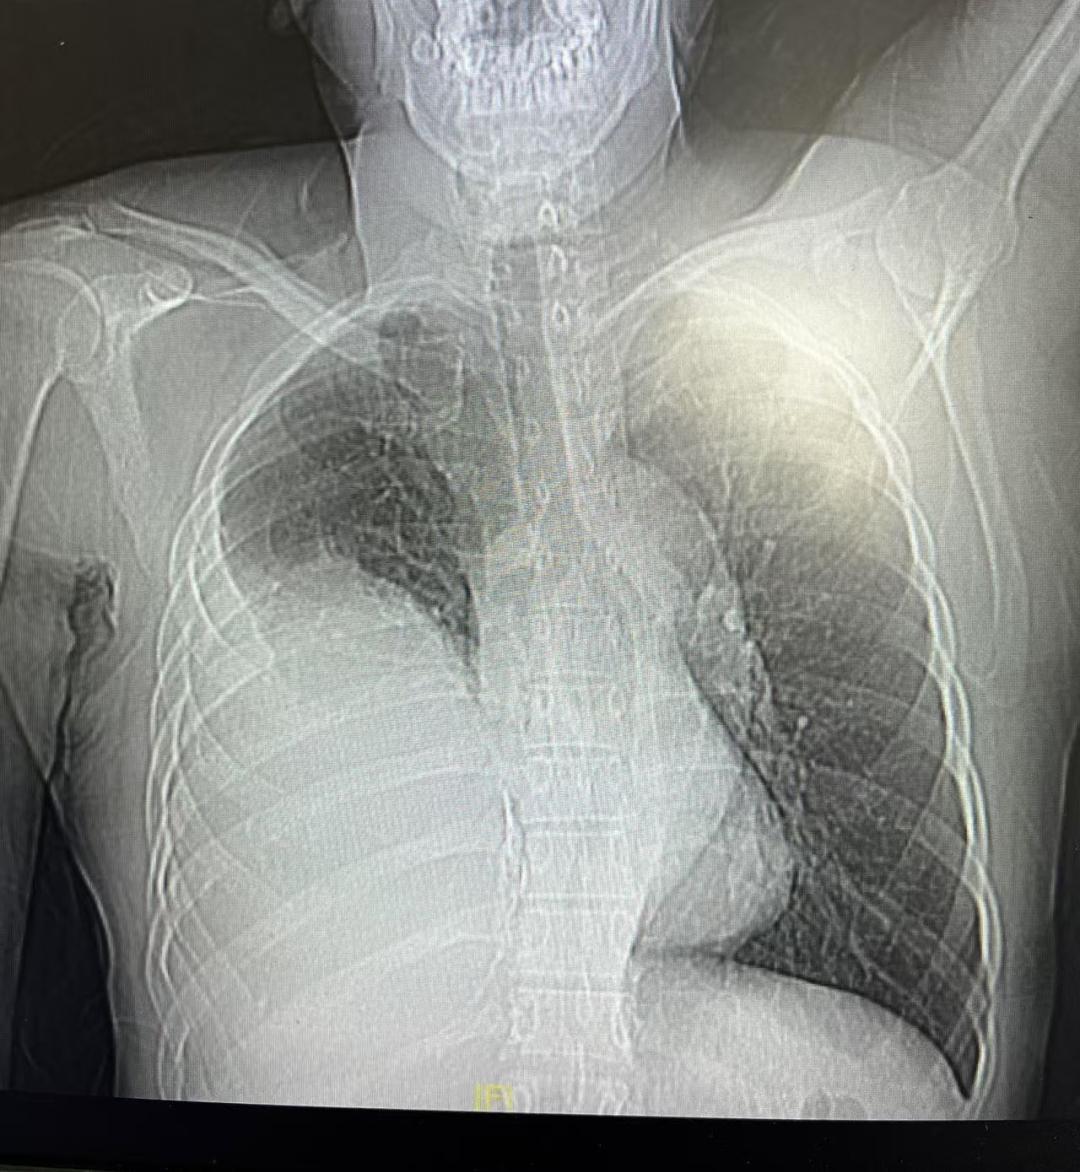

珠江医院的检查结果显示,肿瘤最大截面达17.5厘米×12.6厘米,差不多有一个小西瓜那么大,且与肺、心脏形成致密粘连,右肺的上半部分已经被压迫变硬,完全失去了功能。

巨瘤挤占了半个胸腔。